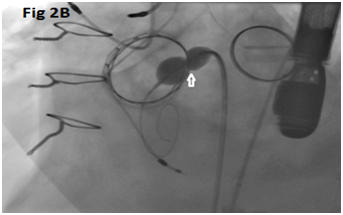

A 73-year-old female with mechanical mitral valve, tricuspid annuloplasty (32mm Edwards Physio Tricuspid incomplete ring) underwent Transcatheter Tricuspid Valve Replacement (TTVR) using off-label 29mm Edwards Sapien 3 (S3) Transcatheter Heart Valve (THV). Immediate post valve deployment, mild Perivalvular Leak (PVL) was noticed at the septal aspect (area of incomplete annuloplasty ring). Eighteen months later, patient presented with recurrent right heart failure and paracentesis due to severe tricuspid PVL (Figure 1A-C, Video 1). Percutaneous PVL closure under general anesthesia, Trans-esophageal Echocardiography (TEE) was performed. Via femoral venous access, defect was easily crossed with Agilis steerable sheath, multipurpose catheter and 0.035” glide wire. Despite recurrent attempts, wire came through the PVL but then traversed through open cells of S3 into the right ventricle (Figure 2A), confirmed with Armada 6mm balloon waist at the S3 cage (Figure 2B) (despite inflating 28mm Z med balloon inside S3 cage, Figure 2C). We decided to partially deploy the plug and assess valve function. Using 7.5F Asahi Eaucath multipurpose guide, a 12mm AmplatzerTM Vascular plug II (AVP II) was advanced through the defect. The ventricular disc was opened inside the S3 cage while body in the PVL defect (outside the S3 cage) and atrial disc on the atrial side of PVL (Figure 3A-B). With S3 function unaffected, no central leak and minimal gradient, PVL reduced to mild severity (Figure 4A-D, Video 2); the AVP II was successfully deployed (Figure 5). At 3-month follow up, there was an excellent symptomatic improvement (NYHA functional class I), with no heart failure re-hospitalization or paracentesis. Deployment of plug disc inside the valve frame is not recommended due to fear of interference with leaflet function and possible injury in long term. There was no immediate issue with the valve function in this case (due to space between the leaflet and frame of S3 and depends on size of plug used). Valve-in-Valve (S3-in-S3) would have certainly sealed all open cells treating this PVL but is more expensive option.

Figure 3 Successful implantation of AmplatzerTM Vascular plug II (white arrows).